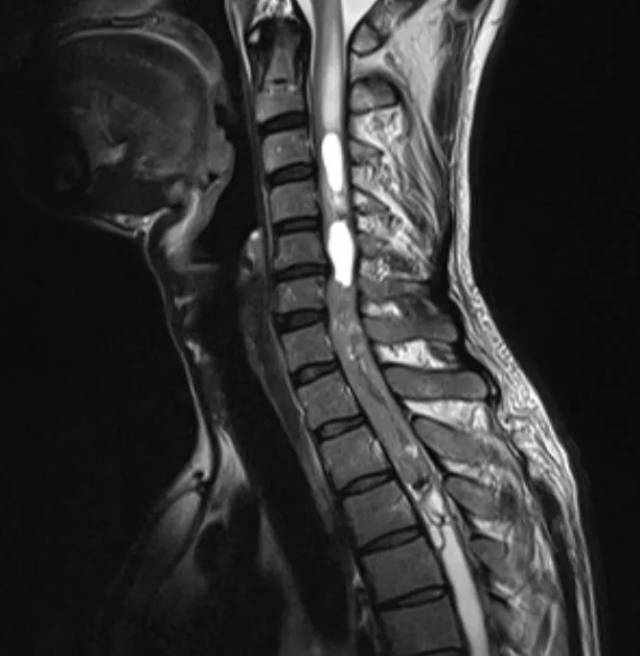

颈椎退行性改变,c6/7椎间盘变性膨出.测量膀胱残余尿量为150ml.

脊髓前后受压,颈3_4平面脊髓变性,颈椎退行性改变

术前颈椎磁共振显示颈椎间盘多节段突出,颈髓受压呈串珠状,颈髓变性!